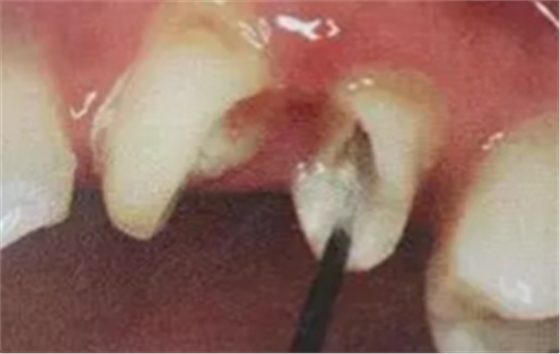

(超聲去除根管殘留物)

通常此時(shí)以超聲潔牙機(jī)更換較細(xì)工作尖進(jìn)入根管(根管消毒沖洗液配合清潔工作后面會(huì)提到),徹底去除樁道根管壁上的附著殘留物,效果明顯。再配合X線片、根管顯微鏡輔助檢查清理的情況下更佳。